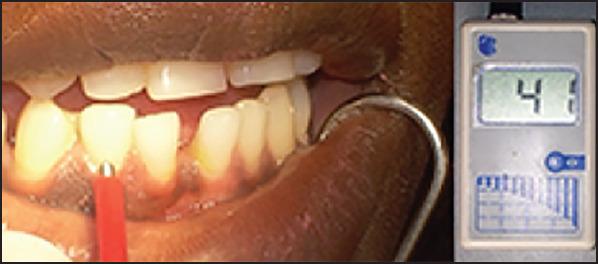

This case report describes the treatment of a double root fracture of a lateral mandibular incisor and its follow- up over 3.5 years. The reason for the consultation was a tooth mobility following a fall that had occurred 2 days earlier. A test of pulp vitality for tooth 42 was positive. Periodontal probing at the level of the gingival sulcus confirmed the intactness of the epithelial attachment. Retro-alveolar radiographic examination revealed a double root fracture of tooth 42. A semi-rigid extra-coronal splinting was performed and a light grinding of the incisal edge of tooth 42 was then carried out in light of the dislocation of the coronal fragment, and the occlusion was checked with a strip of articulating paper. The outcomes at 6 months revealed that pulp vitality was still preserved, consolidation of the apical fracture had occurred, and the coronal root fracture was starting to heal. The 1-year, 2-year and 3-year follow ups revealed preserved pulp vitality, an absence of a fracture line in apical images, and no root resorption. This case report provides evidence for the preservation of vitality in the setting of a double root fracture.

本病例报告描述了一例下颌侧切牙双根骨折的治疗及其3.5年的随访情况。会诊原因是2天前摔倒后牙齿松动。对42号牙的牙髓活力测试呈阳性。在龈沟水平进行牙周探诊证实上皮附着完整。牙槽后位X线检查显示42号牙双根骨折。进行了半刚性冠外夹板固定,然后根据冠部骨折块的移位情况对42号牙的切缘进行了轻度打磨,并用一条咬合纸检查了咬合情况。6个月时的结果显示牙髓活力仍然保留,根尖骨折已愈合,冠根骨折开始愈合。1年、2年和3年的随访显示牙髓活力保留,根尖影像中无骨折线,且无牙根吸收。本病例报告为双根骨折情况下保留牙髓活力提供了证据。